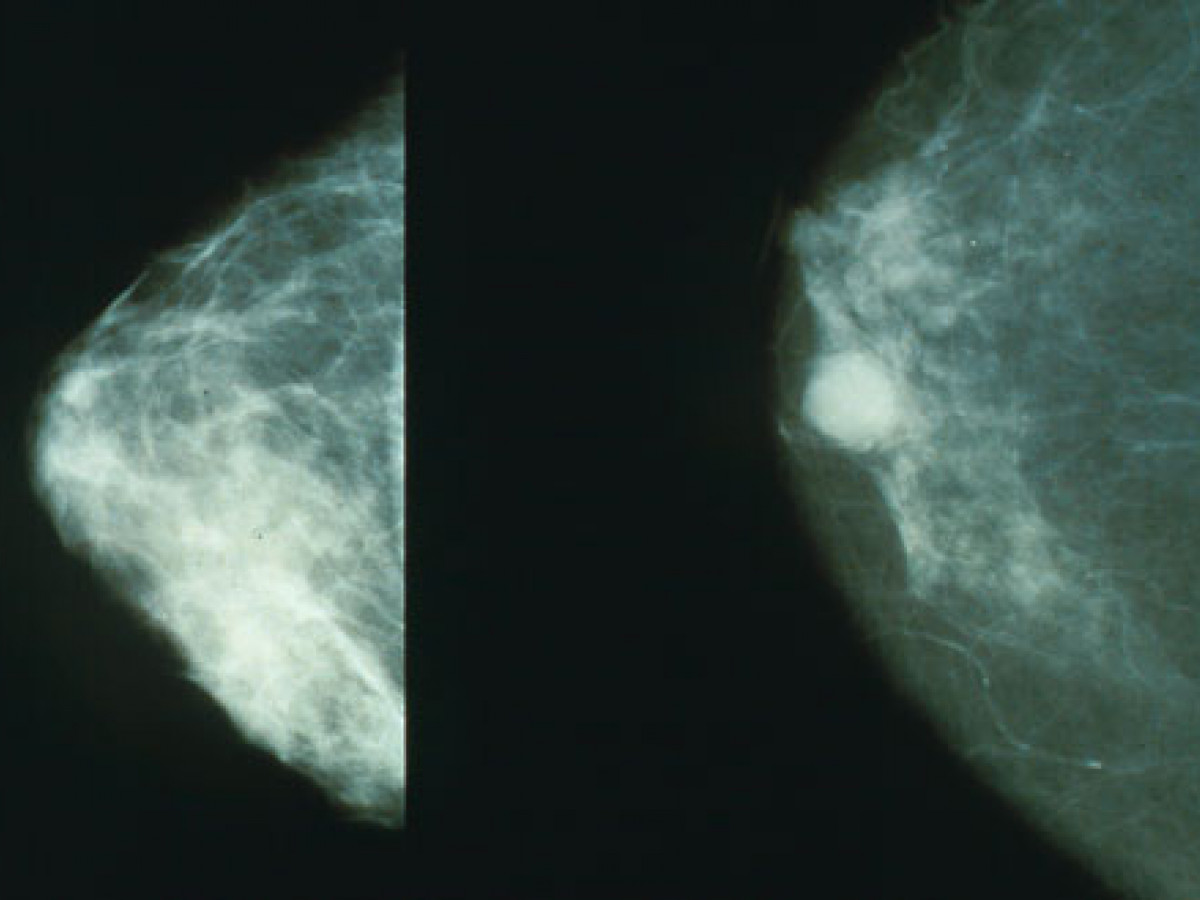

Mammograms

Sometimes the tumours grow deep inside the body. If there is plenty of room for them to grow before they cause symptoms, they can easily become very big and have formed many metastases before the person affected becomes aware of the problem. Lung cancers, stomach cancers and bowel cancers are rather like this.